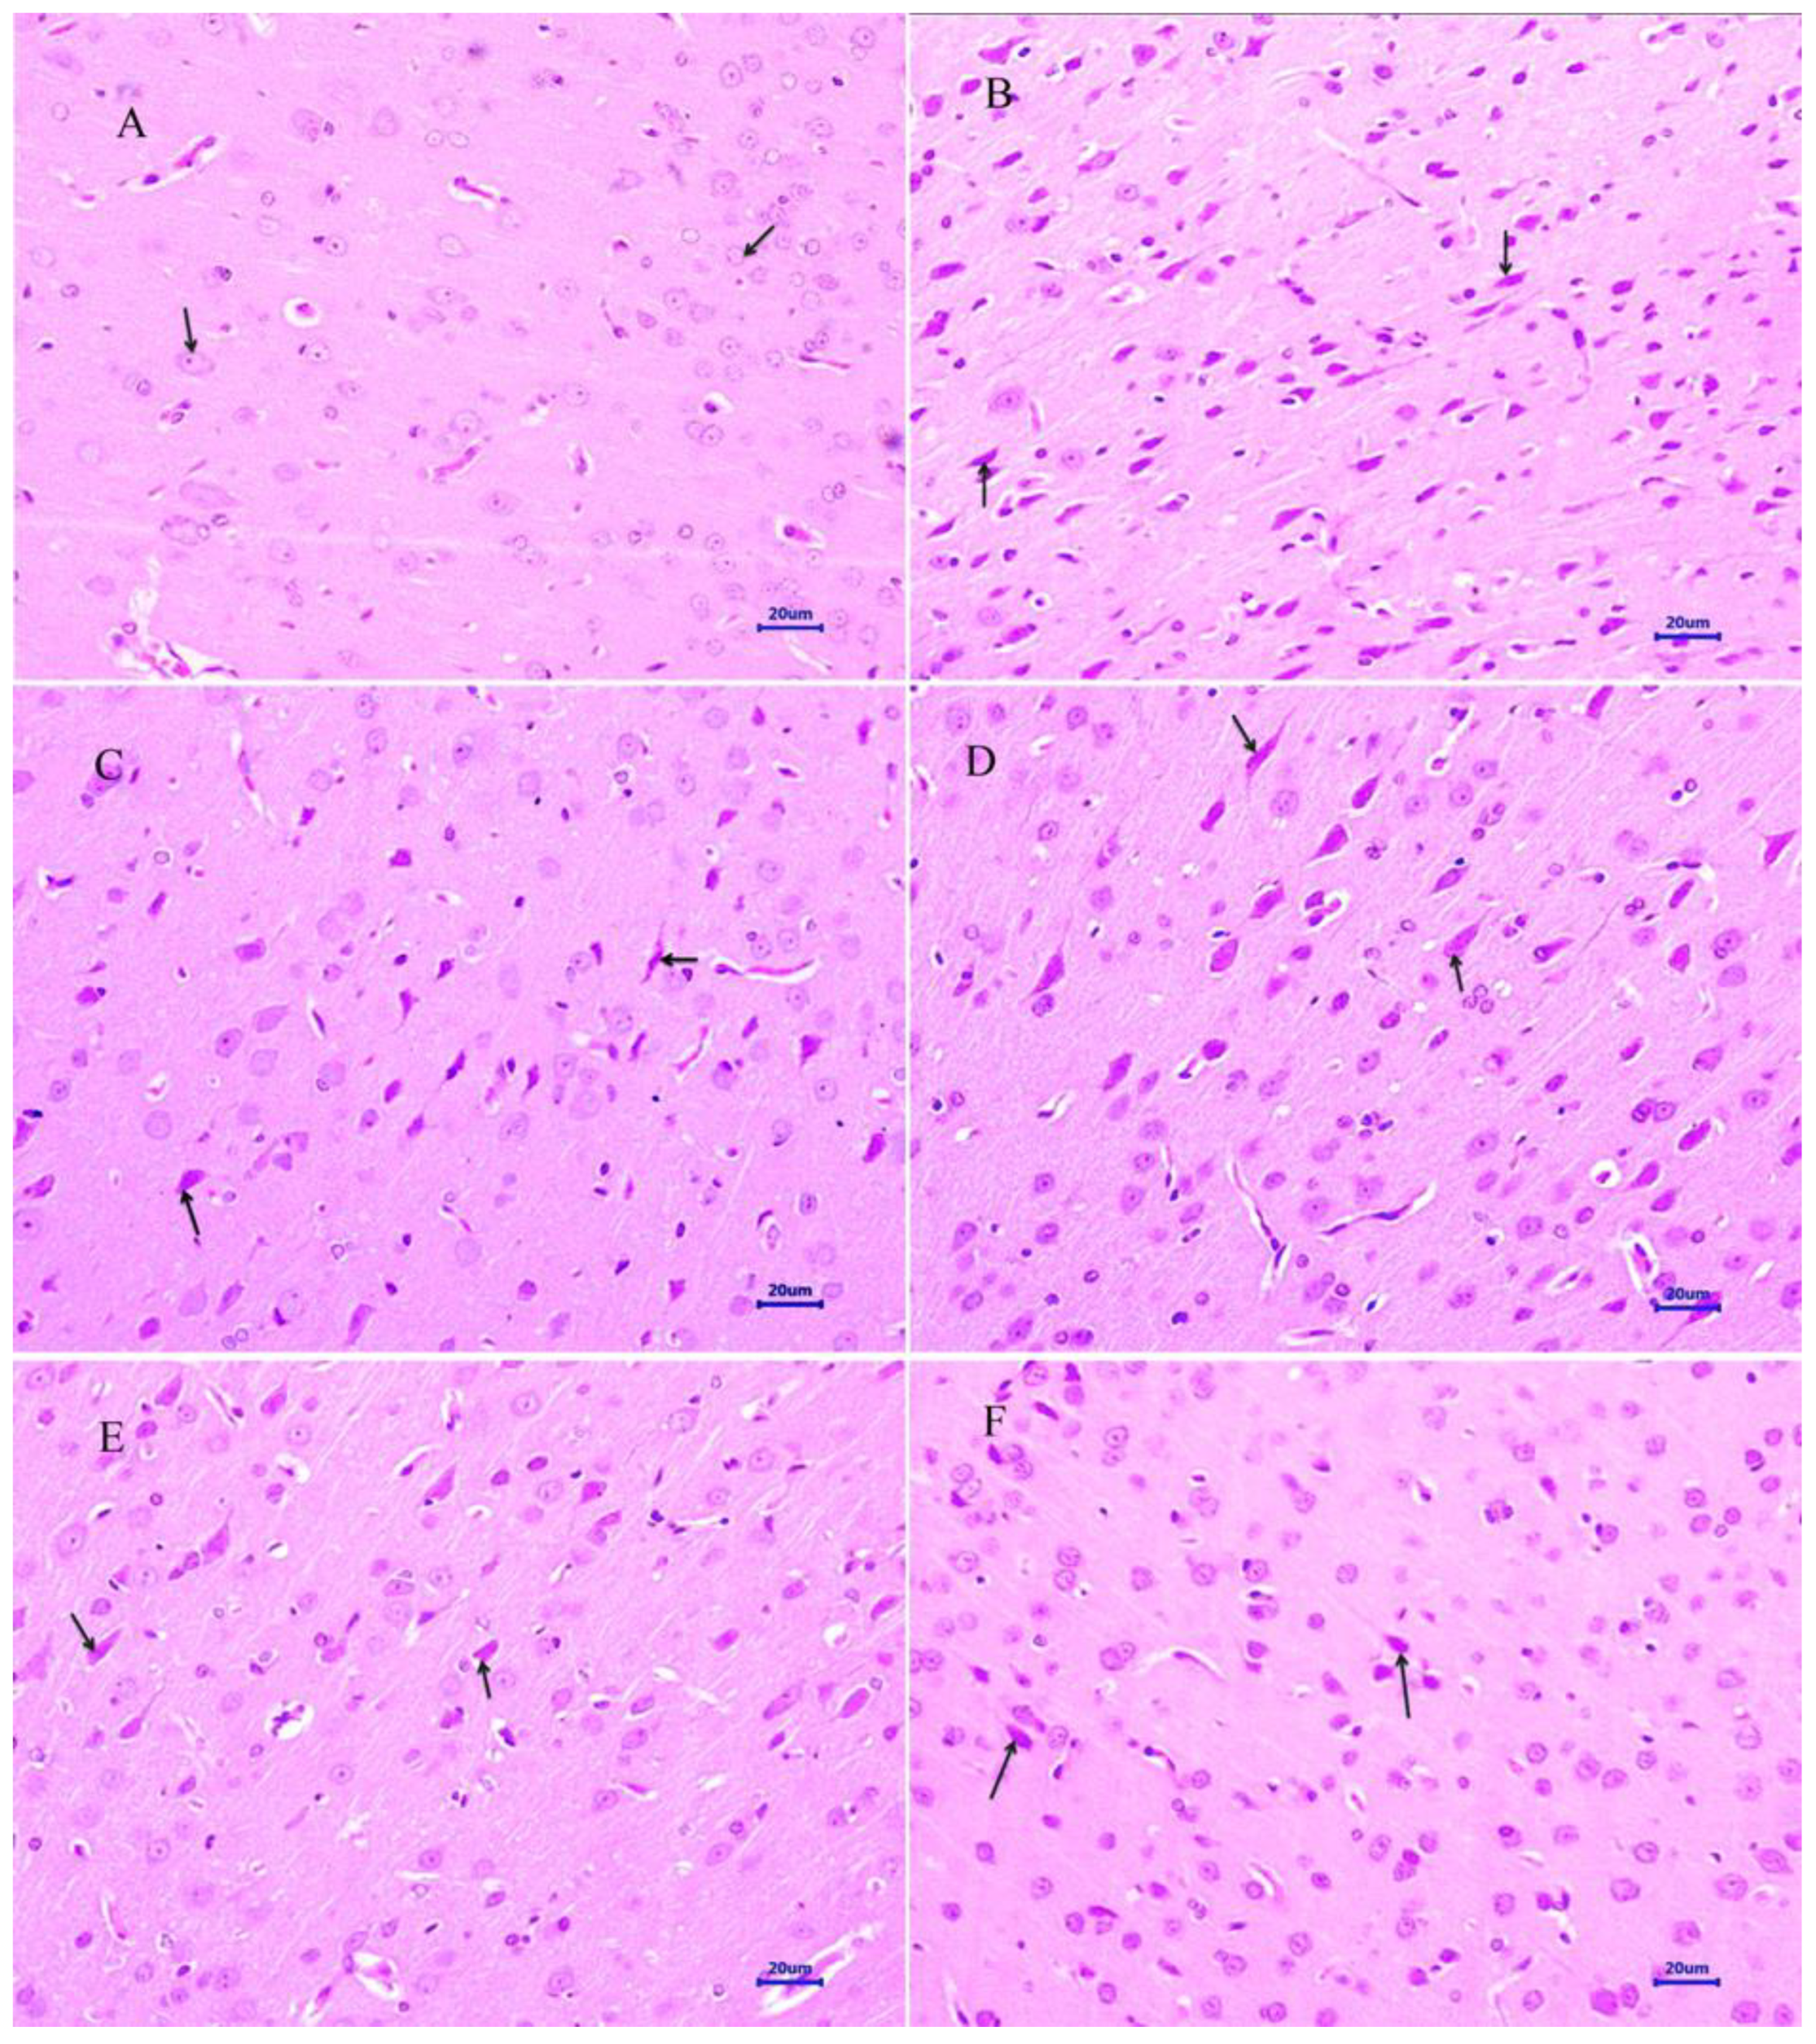

The histopathological assessment of the cortex and hippocampus was performed after staining with hematoxylin and eosin. Microscopic examination of the cortex and hippocampus (Figure 7A and Figure 8A) from normal control group did not show any lesion of pathological significance. The disease control group showed various histopathological changes such as multifocal moderate neuronal degeneration and focal to a multifocal mild-to-moderate reduced layer of neuronal cells in the cortex and hippocampus (Figure 7B and Figure 8B). Treatment with memantine at a dose of 20 mg/kg showed focal minimal to mild neuronal degeneration in the cortex and focal minimal reduced layer of neuronal cells in the hippocampus (Figure 7C and Figure 8C). Moreover, treatment with quercetin 50 mg/kg showed multifocal minimal to mild neuronal degeneration at the cortex and hippocampus (Figure 7D and Figure 8D), additionally focal mild reduced layer of neuronal cells in the hippocampus. Quercetin, when administered with memantine at a dose of 20 + 25 mg/kg (Figure 7E and Figure 8E), showed multifocal minimal to mild neuronal degeneration at the cortex and hippocampus. The treatment group quercetin with memantine at a dose of 20 + 50 mg/kg (Figure 7F and Figure 8F) showed focal minimal neuronal degeneration at the cortex and hippocampus, which indicated an improvement in comparison to the disease control group. The arrow indicates the histopathological changes.

Figure 7.

Effect of quercetin and quercetin administered with memantine on H&E-stained cortex tissue (400×). (A): Normal control, (B): Disease control, (C): Memantine (20 mg/kg), (D): Quercetin (50 mg/kg), (E): Memantine + quercetin (20 + 25 mg/kg), (F): Memantine + quercetin (20 + 50 mg/kg).

Figure 8.

Effect of quercetin and quercetin administered with memantine on H&E-stained hippocampus tissue (400×). (A): Normal control, (B): Disease control, (C): Memantine (20 mg/kg), (D): Quercetin (50 mg/kg), (E): Memantine + quercetin (20 + 25 mg/kg), (F): Memantine + quercetin (20 + 50 mg/kg).

Microscopic examination of the cortex and hippocampus stained with hematoxylin and eosin (H&E) showed various lesions among different groups. Examination of the cortex and hippocampus of rats from the normal group did not show any lesion of pathological significance. By contrast, brain tissues from the disease control group showed multifocal moderate neuronal degeneration at the cortex and hippocampus. Animals treated with quercetin and memantine showed focal minimal neuronal degeneration at the cortex and hippocampus. It demonstrated that treatment of quercetin with memantine at a dose of 20 + 50 mg/kg had reversed the neurotoxic effect of the AlCl3 due to its neuroprotective activity. The extent of deposition of Aβ plaque in the brain was assessed using Congo red stain, and it was observed multifocal moderate deposition of amyloid-β in the cortex and hippocampus of disease control animals, which were absent in the normal control group. The treatment of quercetin with memantine at a dose of 20 + 50 mg/kg showed minimal to mild deposition of amyloid-β at the cortex and hippocampus, indicating that it is effective in inhibiting the expression.